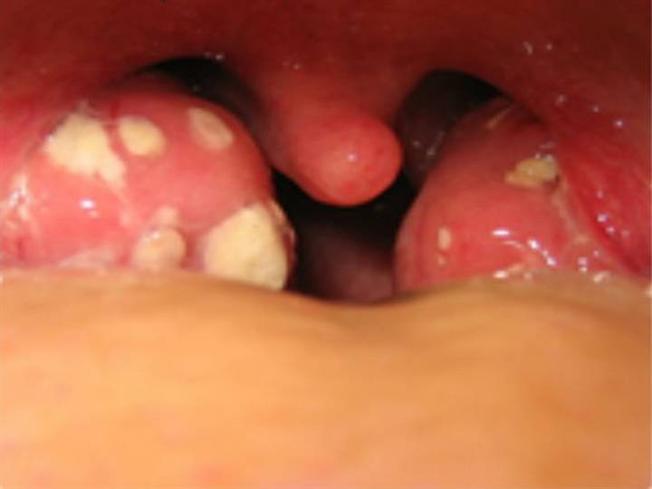

При ангине поражаются в первую очередь миндалины, затем ротовая полость. Первоначальным признаком ангины является непосредственно воспалительный процесс небных миндалин. Начальная стадия данного заболевания отмечается высокой болью в области горла.

Как распознать ретрофарингеальный абсцесс? Главным симптомом, который видно невооруженным глазом, будет выбухание, чаще одностороннее, стенки глотки. Конечно, присутствуют и другие симптомы — у больного, как и при обычной ангине, снижается аппетит и значительно повышается температура, присутствует сильная слабость ввиду интоксикации организма.

Есть еще одна причина этого осложнения. Некоторые пациенты пытаются самостоятельно очистить содержимое лакун с помощью различных предметов. Этого делать категорически нельзя! Поверхность миндалин очень нежная и моментально начинает кровить. Кроме того, эта процедура нецелесообразна в острый период заболевания — налеты, которые видны глазу физически почти невозможно полностью отделить от миндалины. И на месте удаленных кусочков в скором времени появляются новые.